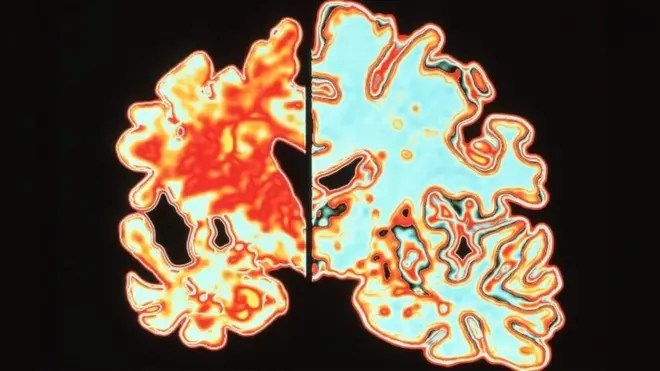

มันยังมีสิ่งสำคัญที่ไม่รู้อีกมากมาย และยังไม่มีคำอธิบายที่ชัดเจนว่าทำไมการเชื่อมต่อระหว่างเซลล์ประสาทที่เรียกว่าไซแนปส์ (synapses) จึงสูญหายไปในโรคอัลไซเมอร์

ทีมงานจะนำชิ้นเนื้อสมองไปสัมผัสกับโปรตีนพิษที่เรียกว่าอะไมลอยด์ (amyloid) และเทา (tau) ซึ่งสะสมในสมองของผู้ป่วยอัลไซเมอร์ เพื่อให้พวกเขาเห็นการทำลายไซแนปส์และหาวิธีหยุดยั้งมัน

เลแคเนแมบ (lecanemab) และโดนาเนแมบ (donanemab) ต่างมุ่งเป้าไปที่โปรตีนเหนียวเป็นพิษที่เรียกว่าอะไมลอยด์ ขณะนี้มีการทดลองทางคลินิกของยาที่มุ่งเป้าไปที่โปรตีนอีกชนิดคือเทา (tau)

นอกจากนี้ ความสำคัญของระบบภูมิคุ้มกัน การอักเสบ สุขภาพของหลอดเลือด และการผสมผสานระหว่างพันธุกรรมกับสิ่งแวดล้อม ล้วนช่วยเพิ่มความเข้าใจเกี่ยวกับโรคอัลไซเมอร์